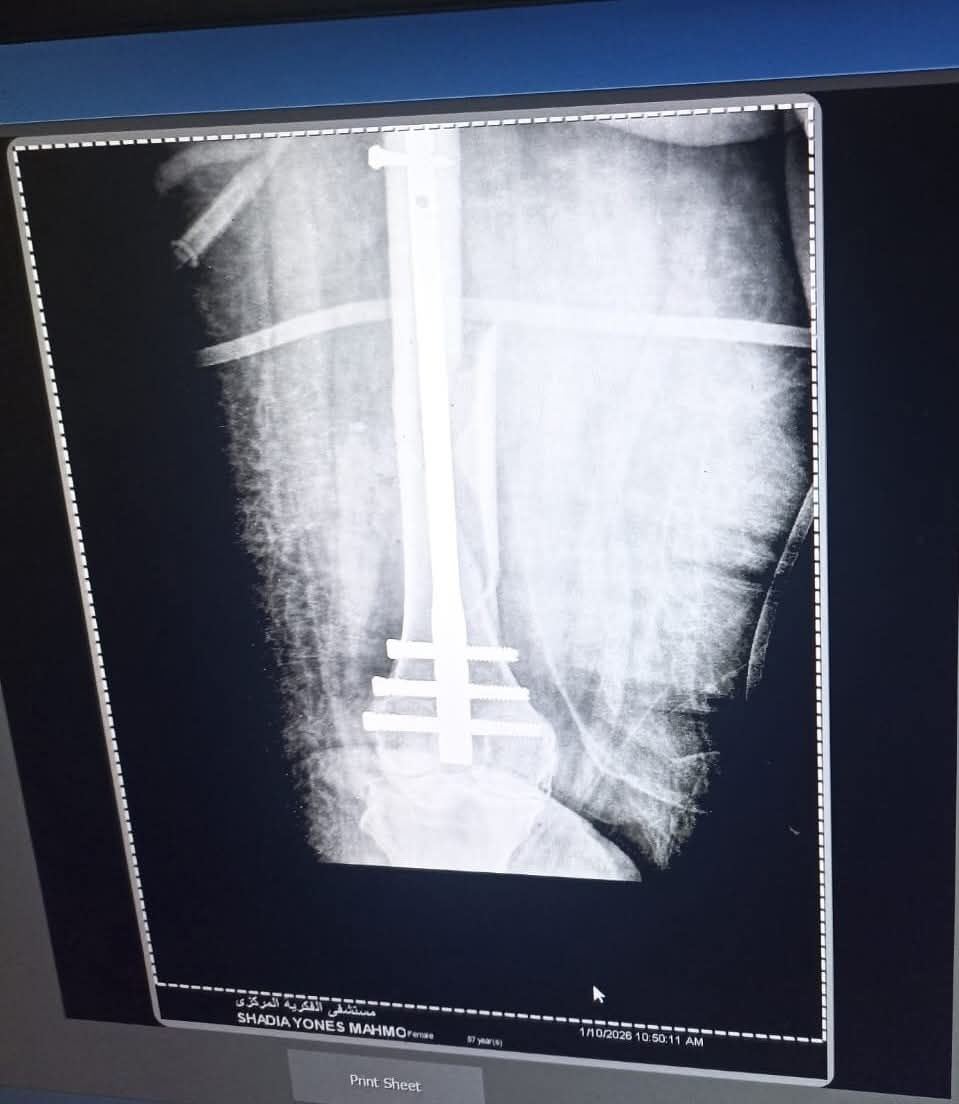

تقنية المسمار النخاعي الارتجاعي (Retrograde Nail):

في خطوة طبية متقدمة، تم التدخل الجراحي وتثبيت الكسر باستخدام "المسمار النخاعي الارتجاعي" عن طريق مفصل الركبة، وهي تقنية حديثة تتطلب مهارة فائقة، خاصة في التعامل مع حالات الأوزان المرتفعة، مما يسمح للمريضة بالتعافي السريع والعودة للحركة في وقت قياسي.

تكللت العملية بالنجاح التام بفضل التنسيق المتكامل بين نخبة من الكوادر المتميزة: